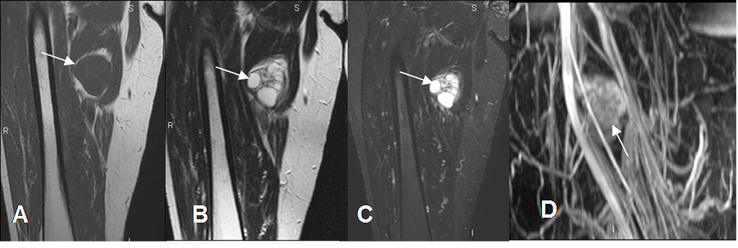

Fig 13. Hematoma muscular agudo.

A: RM coronal en T1. Colección hipointensa sobre los aductores, que corresponde a hematoma agudo.

B: RM coronal en T2 y C: RM coronal en STIR. Colección hiperintensa en ambas secuencias.

D: AngioRM coronal. Hematoma que produce efecto de masa y desplaza los vasos femorales.